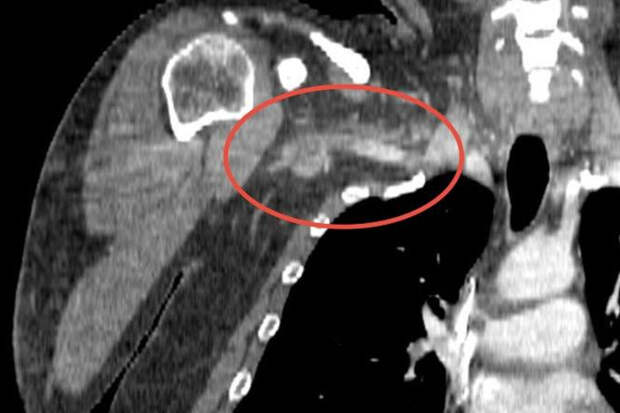

"Причиной артериального тромбоза оказался огромный 25-сантиметровый сгусток тромболитической массы, закупоривший сосуды от плеча до шеи. В ходе 1,5-часовой операции мы удалили тромб с помощью специального баллона, который, расправившись, контролируемо продвинул сгусток далее по сосуду к разрезу в районе локтевого сгиба. Там мы зацепили его специальным крючком и благополучно извлекли", - поделился сосудистый хирург больницы Михаил Пырля.